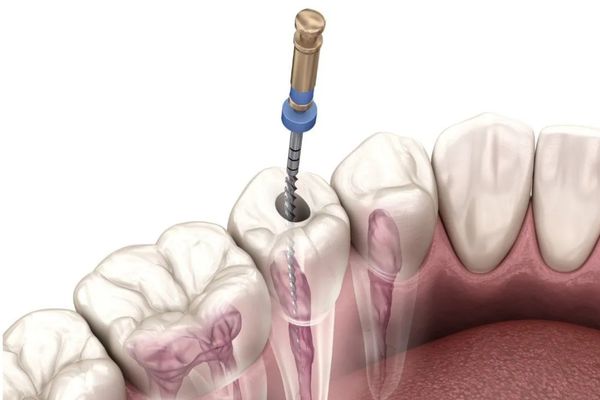

Tomografia para

Endodontia (Tratamento de Canal)

A Tomografia para Endodontia utiliza a tecnologia CBCT com um campo de visão (FOV) reduzido, focando apenas nos dentes de interesse. Este nível de detalhe tridimensional é essencial para o tratamento de canal, pois permite ao dentista visualizar canais radiculares acessórios, fraturas, reabsorções internas ou externas, e diagnosticar a extensão de infecções que não são claramente visíveis em radiografias 2D. É uma ferramenta de precisão que eleva o diagnóstico endodôntico, contribuindo diretamente para a melhora na qualidade de vida e o sucesso a longo prazo do dente tratado.